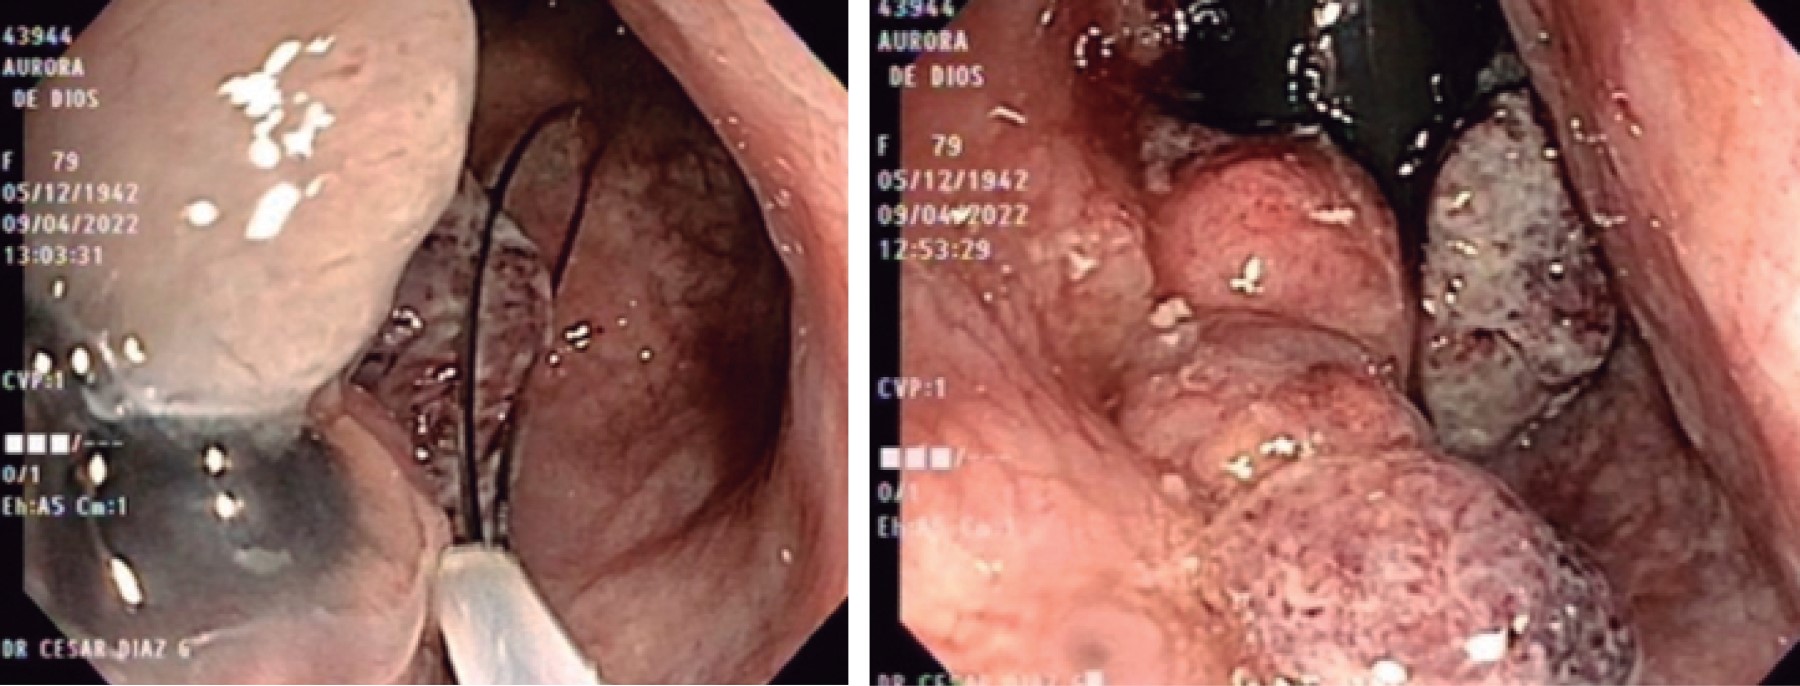

A 79-year-old female patient with no previous history of importance went to the general medicine outpatient clinic for presenting transrectal bleeding and diarrheal bowel movements of approximately one week of evolution, which was managed as hemorrhoidal disease, and topical treatment was provided for two months. However, she persisted with the same symptomatology in addition to the sensation of an anal mass and pain at the same level, so she went to the coloproctology service, where a physical examination found a typical perianal region without evidence of lesions; rectal examination revealed an induration of approximately 5 × 5 centimeters in the anal canal at left lateral level, so a colonoscopy was performed that showed evidence of an elevated tumor in the rectal ampulla of polypoid appearance of approximately 20 mm with hyperemic, edematous and friable mucosa. A biopsy was taken with a polypectomy loop (Figure 1), with a histopathological report of undifferentiated and ulcerated malignant neoplasm of the anorectal region; an immunohistochemistry study was performed with positive results for Melan A and HMB 95, and a diagnosis of an ulcerated malignant melanoma was made. Extension studies were performed with simple thoracoabdominal-pelvic computed tomography scan and intravenous contrast, without evidence of metastatic disease or inguinal adenopathies, reporting thickening of the walls of the rectum up to 50 mm with annular morphology. An MRI showed a lesion in the lower rectum/anal canal, without changes in perirectal fat, without alterations in adjacent mucosa.

Figure 1